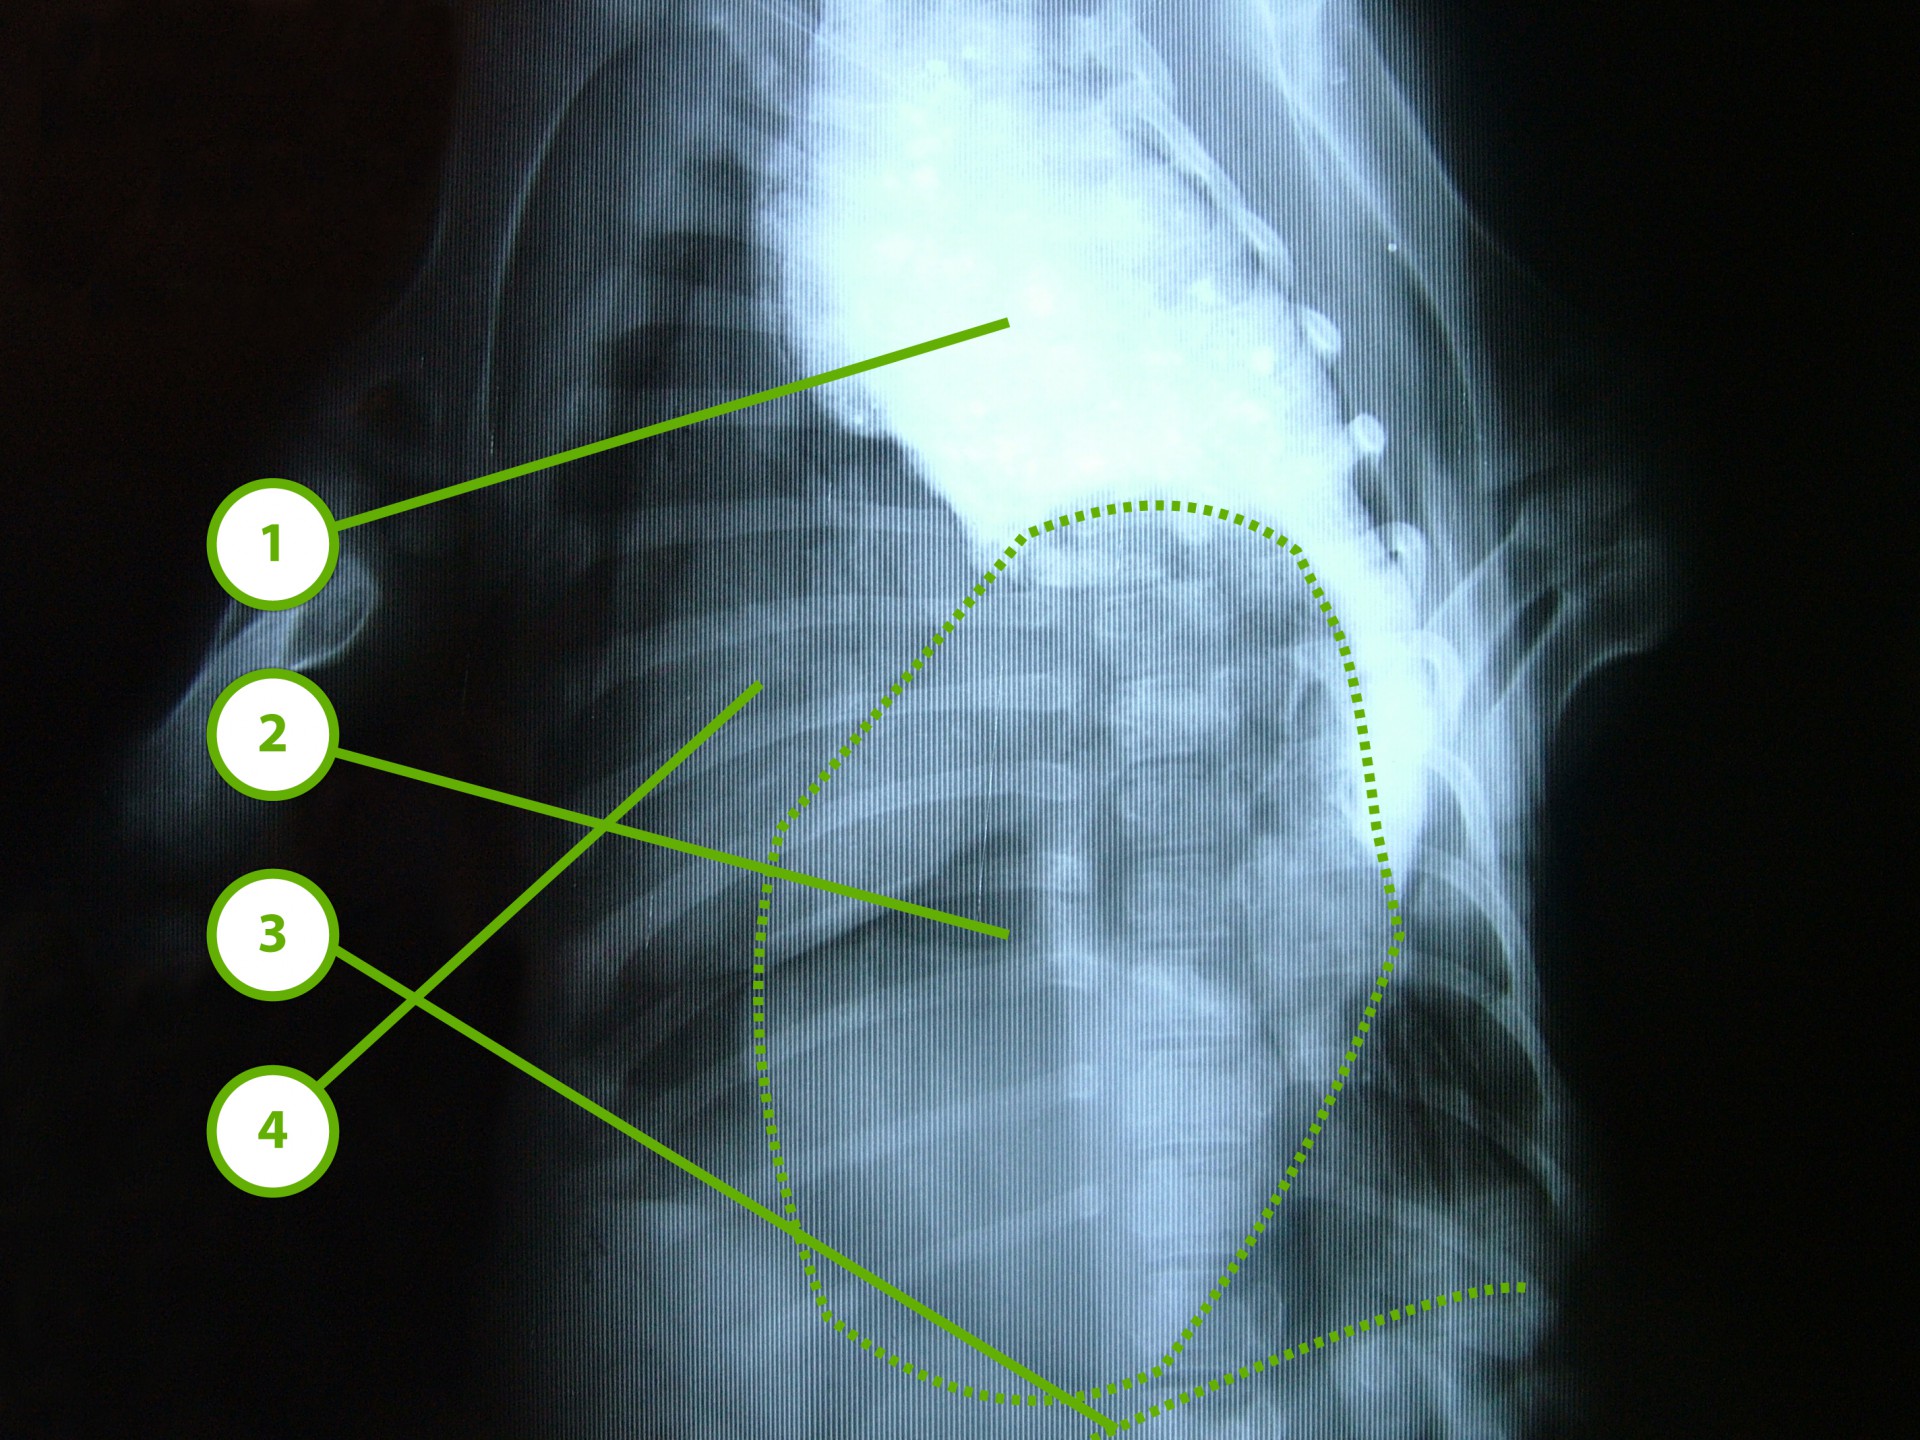

A rekeszizom veleszületett vagy szerzett sérülése, folytonosság hiánya következtében a hasüregi szervek a mellkasba nyomulnak, és összenyomják a tüdőt. Ennek következtében a tüdő nem képes a mellkas mozgását követni és elsősorban a belégzés folyamata korlátozottá válik.

• A fejlődési rendellenesség következtében kialakuló veleszületett rekeszsérv (hernia diaphragmatica congenitalis ) általában fiatal állatokban, alapvetően kétféle formában jelenik meg: az egyik formában a rekeszizom kisebb-nagyobb, a teljes vastagságára kiterjedő folytonossághiánya következtében a hasüregi szervek egy része a mellüregbe nyomul (valódi veleszületett rekeszsérv, hernia diaphragmatica congenitalis vara ).

Mindhárom rekeszsérv forma meglehetősen ritkán fordul elő. A diagnózis felállítása a kórelőzmény, a klinikai tünetek a mellkas röntgenvizsgálata, a hasüreg ultrahangos vizsgálata alapján lehetséges.A rekeszsérv műtéti ellátása során a legnagyobb kihívást az jelenti, hogy a hasüreg megnyitását követően a sérvkapun keresztül levegő kerül a mellüregbe, ezáltal az állat spontán légzése leáll, így a műtét teljes ideje alatt asszisztált lélegeztetésre van szüksége.A műtét során a mellkasba előesett szerveket reponáljuk, a rekesz folytonosság hiányát megszüntetjük és a mellkasban lévő szabad levegőt eltávolítjuk, ezzel biztosítva az állat spontán légzését. A műtétet követő napokban legfontosabb feladat a vérkeringés és a légzés folyamatos, kórházi körülmények közötti kontrolálása.Az idejében felismert és megfelelően ellátott veleszületett rekeszsérv jó eséllyel gyógyítható, a traumás eredetű sérv ellátásának eredményességét általában az egyéb szervek sérülése határozza meg.